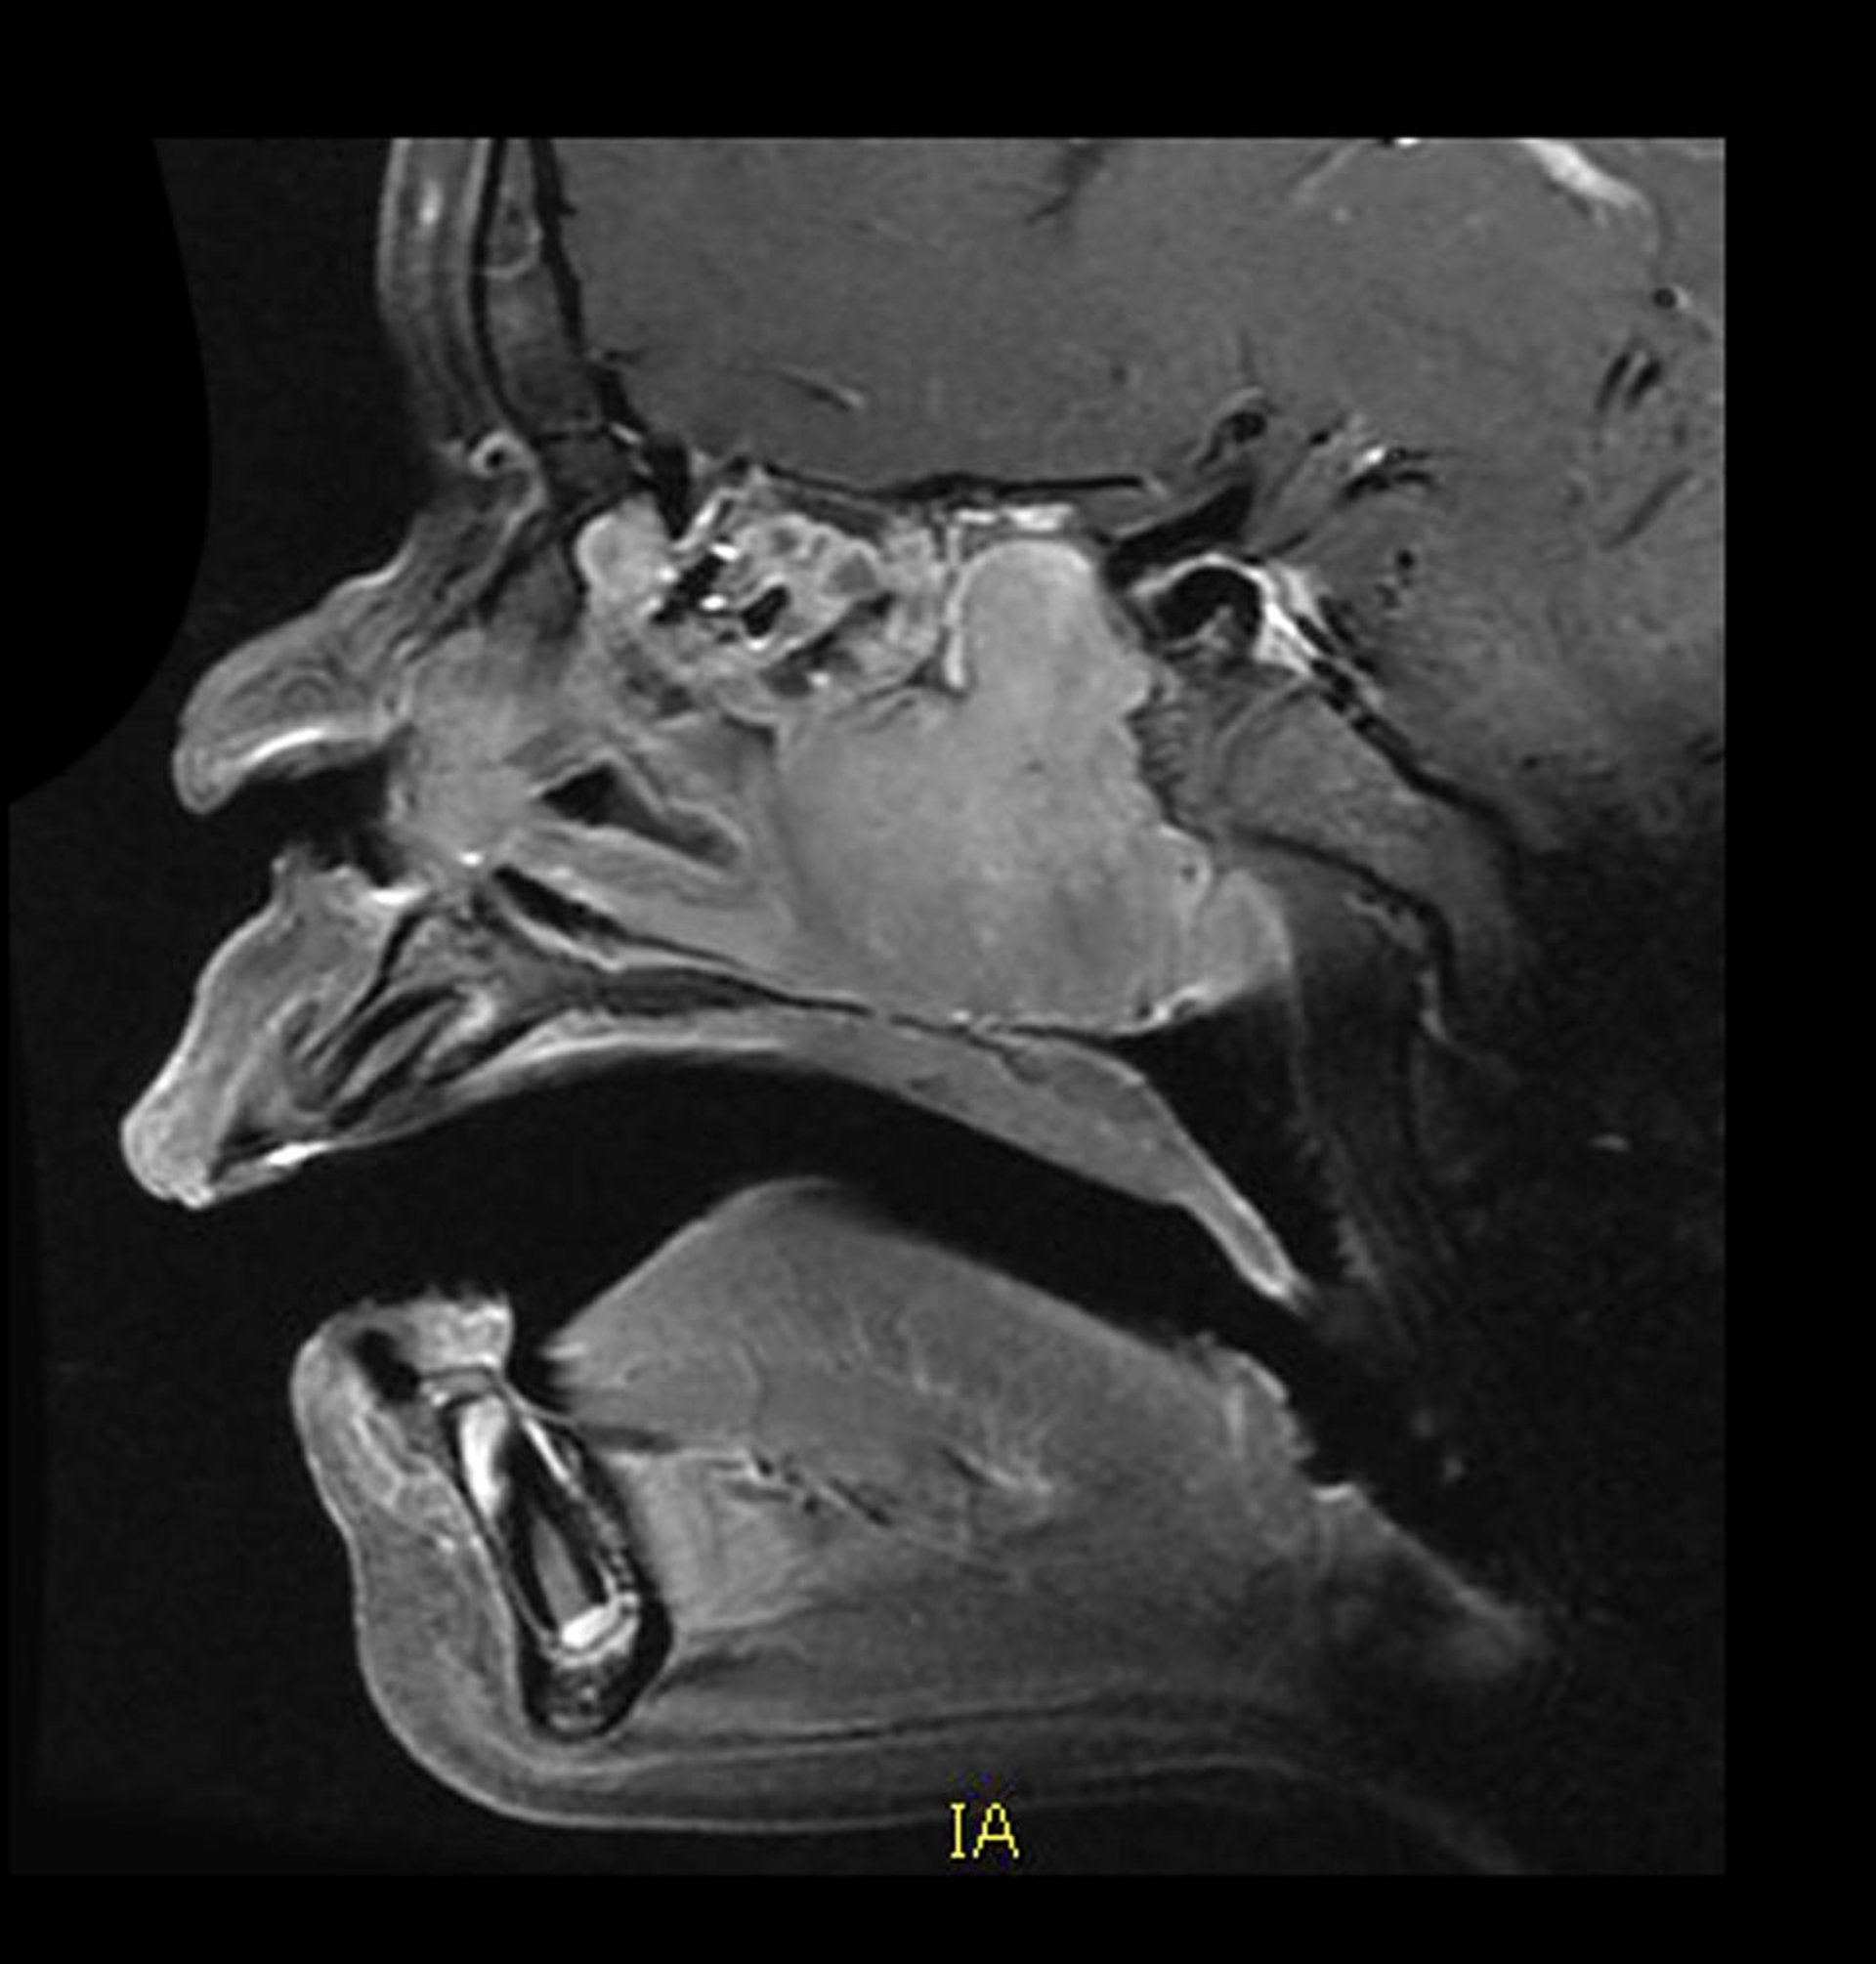

Angiofibroma nasofaríngeo juvenil (RM)

Esta RM sagital con contraste muestra la ubicación y el aspecto típicos de un angiofibroma nasofaríngeo juvenil vascular. Hay una masa con refuerzo homogéneo en la cavidad nasal posterior que crece posteriormente hacia el seno esfenoidal. También hay destrucción ósea asociada.